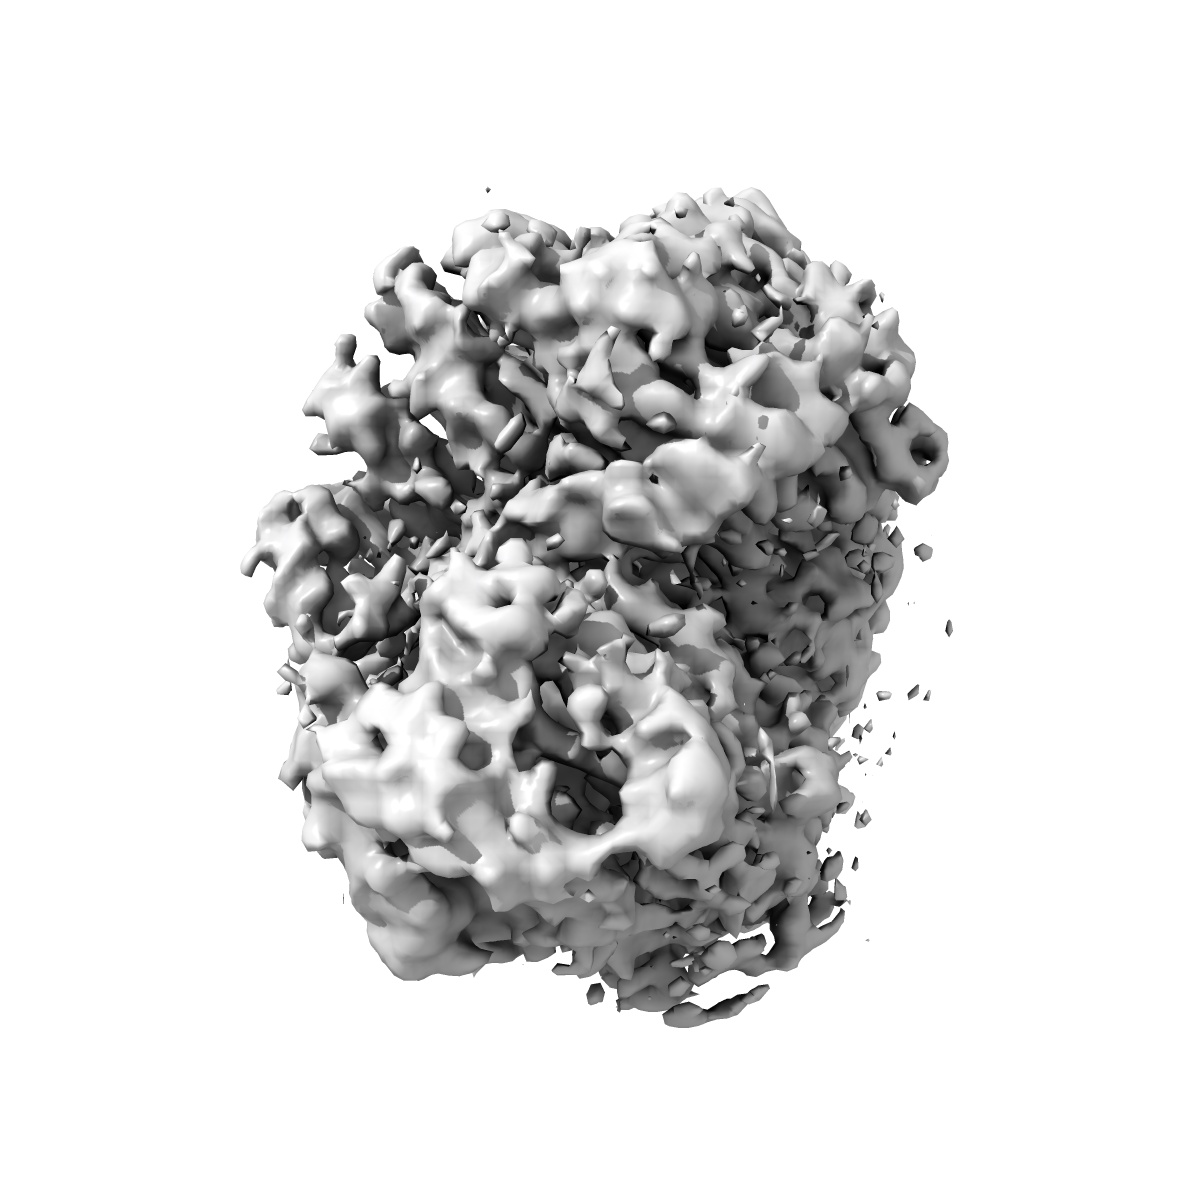

Cryo-EM Structure of the BRAF V600E monomer bound to PLX8394

Single-particle3.06 Å

Sample: BRAF V600E - 14.3.3 complex bound to PLX8394

BRAF oncogenic mutants evade autoinhibition through a common mechanism.

(2025) Science , 388 , eadp2742 - eadp2742